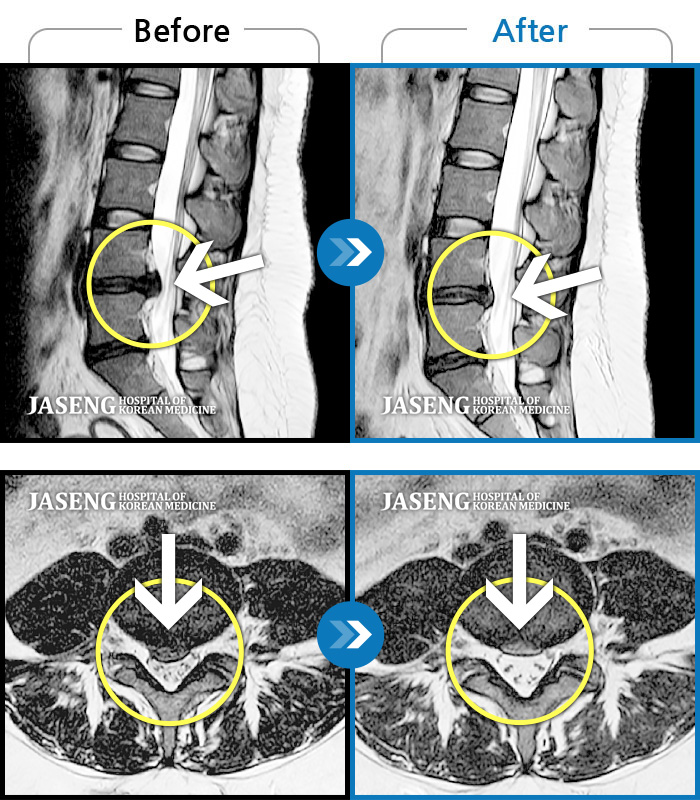

MRI ũ ʸ Ȯϼ.

[ؿ] 24.10.10~25.04.23